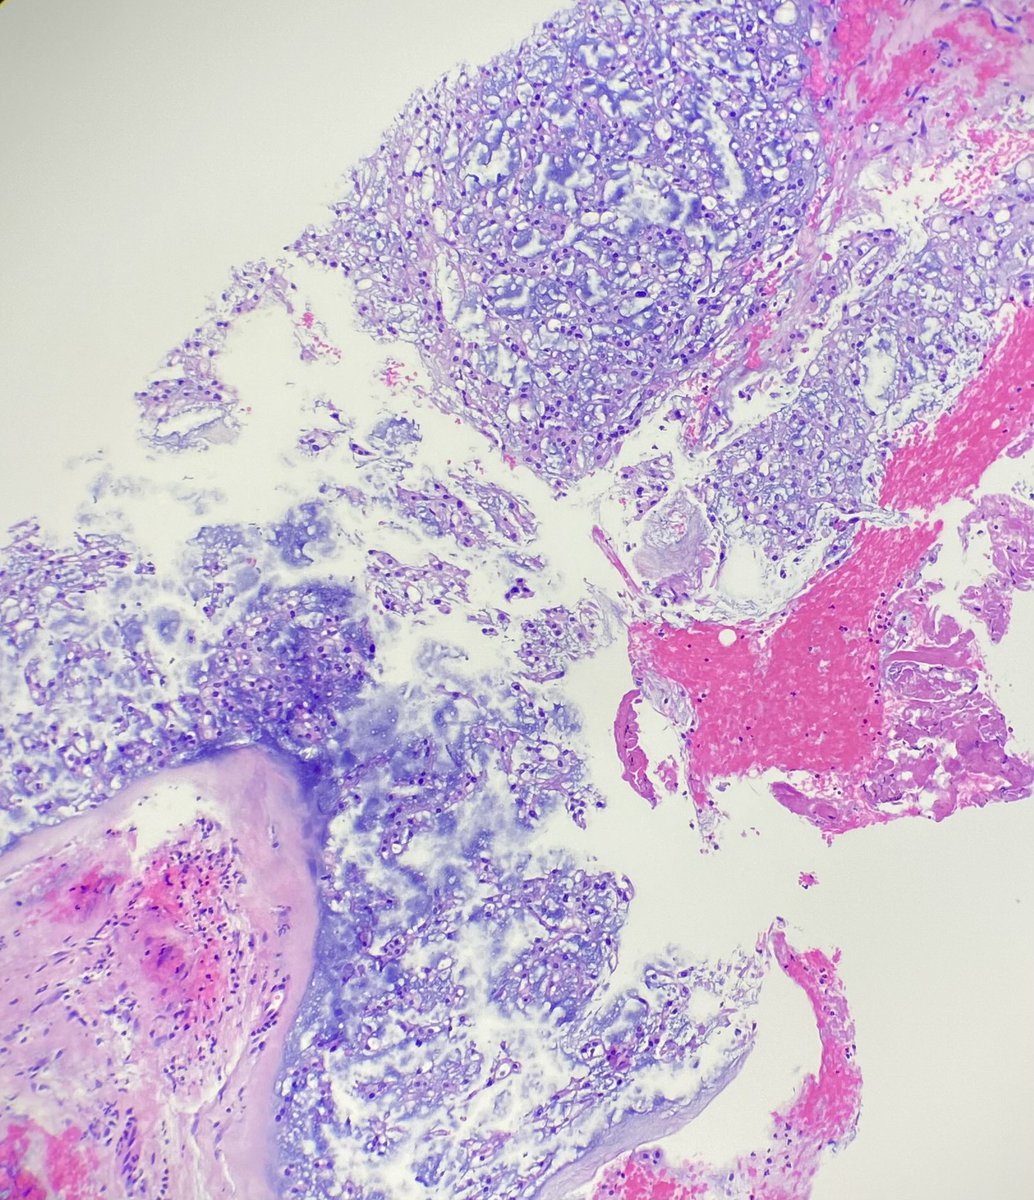

What’s the diagnosis of this spindle cell lesion of breast? 🪡🔬 Poll in the comments 👇 Answer reveal on Monday! 🙌 #PathX #PathTwitter #breastpath